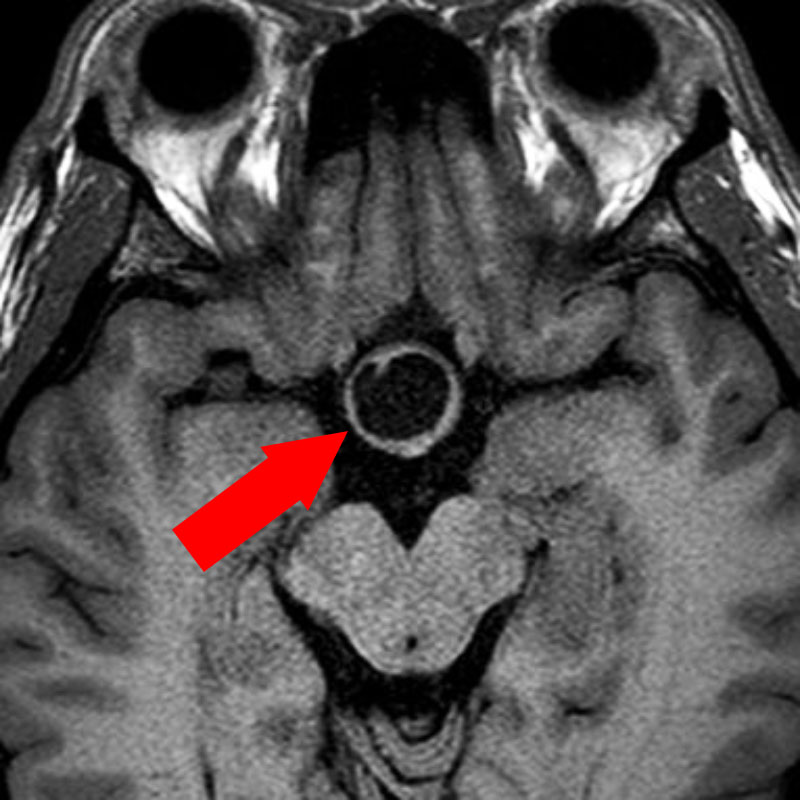

412

'23年5月

20代

小脳血管芽腫

頭蓋内腫瘍摘出術

No.’23_46 手術前1

No.’23_46 手術前2